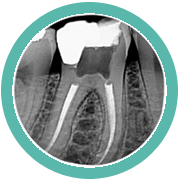

PERIAPICAL

Sirven para explorar el diente en su totalidad, desde la corona hasta el ápice, el espacioperiodontal y el tejido óseo que lo rodea. Se pueden realizar mediante dos procedimientos: la técnica de bisección y la de paralelismo.